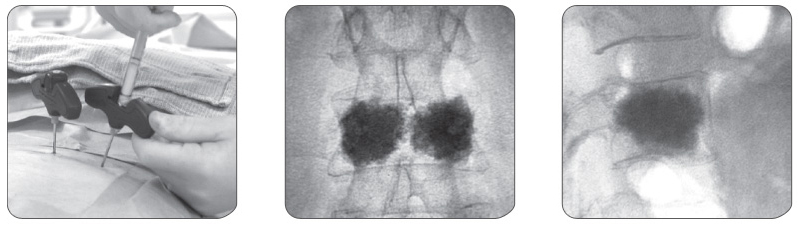

경피적 척추 성형술은 척추체 내부에 골 시멘트를 주입하는 시술법 입니다.

이것은 원래 척추체에 생긴 혈관종의 치료나 종양 침범으로 인한 골절 및 통증을 치료하고자 시작된 것으로

현재는 골다공증성 압박 골절의 치료에 광범위하게 이용되고 있습니다.